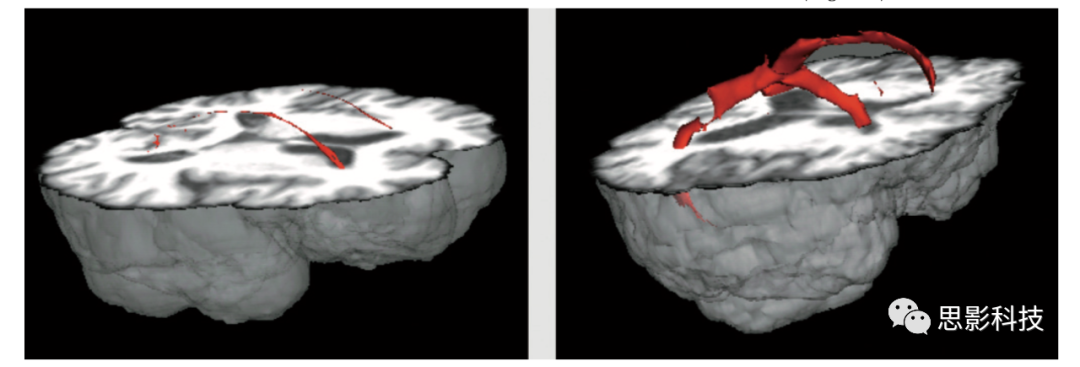

WMH有時被稱為腦白質疏松或腦白質病,表現(xiàn)為T2高信號。大量臨床和老化研究中對WMH進行了豐富研究,并存在較多爭議,一部分認為WMH是偶然的無臨床意義,一部分認為WMH是認知、運動和情緒功能障礙的主要來源。最初,WMH被描述為“不明原因亮點(unidentifiable bright objects)”,放射醫(yī)師混淆其為人工來源或者老化伴隨產物。實際上,年齡與WMH嚴重程度的相關性最強,大多數(shù)老年人均存在WMH負擔。圖1展示了典型廣泛分布WMH,圖22例老年人,一例為輕度WMH,一例是更為嚴重WMH。WMH通常出現(xiàn)在側腦室周圍的白質(如:“室周”WMH),向深部白質和灰質核團深入(深部”WMH),或作為皮層深部組織中有邊界的點狀球體。值得注意的是,點狀WMH常孤立出現(xiàn)在MRI軸位面,但在三維重建中,通常在同側側腦室同一主干分布。

老年人腦白質高信號嚴重程度的最優(yōu)表征一直備受爭議。部分研究人員認為室周WMH在臨床中不如深部WMH重要。部分研究人員強調了WMH區(qū)域及分布的重要性。這些特征反映在許多視覺評分量表中,例如Scheltens量表,評估WMH的嚴重程度和分布的常用方法。本實驗室開發(fā)了一種局部WMH嚴重程度分析的定量方法。簡單地說,通過考慮每個被試FLAIR圖像的體素強度分布,將高斯曲線擬合到每個大腦半球,并推導出每個半球的均值和標準差,WMH種子點被定義為高于或等于平均值2.5倍標準差。左邊和右邊的種子點被合并,然后每個種子點被傳遞到一個基于平均強度的局部生長算法。該算法使用種子點體素強度作為其起始平均值,并應用10點連接方案(x-y平面,1個在z平面上,1個在z軸下),搜索并標記落在種子均值5%以內的體素。相鄰體素信號下降低于5%被添加到圖像中,并創(chuàng)建一個新的平均值。該過程不斷迭代,直到所有種子都包含在最終的WMH圖像中。標記為WMH的體素數(shù)量乘以體素維度得到WMH總體積。通過對每張圖像進行空間標準化至解剖圖譜,可得到主要解剖腦葉、基底節(jié)區(qū)及小腦WMH體積。圖3展示了FLAIR圖像三個正交視圖,其中標記WMH并進行局部分割。此外,通過對側腦室分割(圖4),可以計算每個體素至側腦室壁的三維距離。因此,該定量處理方法可以用來導出WMH的總體積、局部WMH體積,以及室周和深部WMH體積。